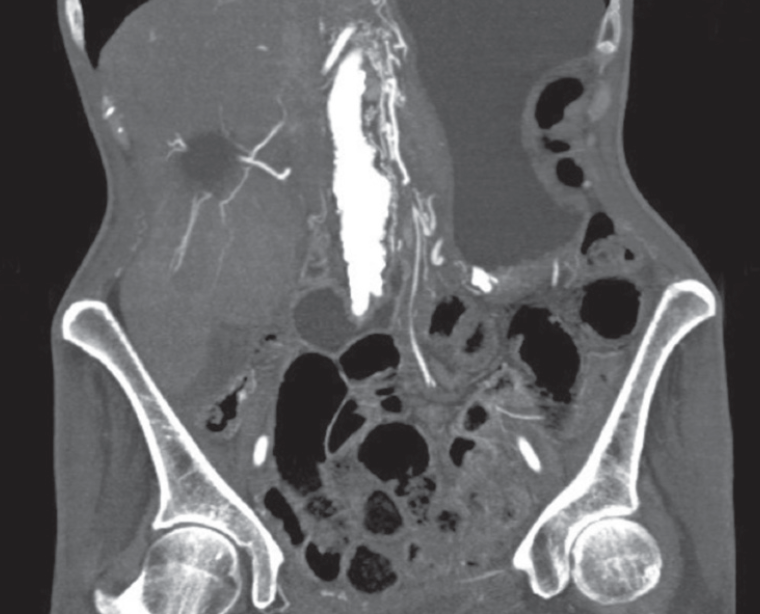

Carolyn Jones; Carolyn J. Sachs, MD, MPH; Shawn Kaku, MD

<p>Because abdominal pain is such a common chief complaint, arriving at an exact diagnosis is often challenging. The dangerous triad of vascular emergencies (mesenteric ischemia, abdominal aortic...